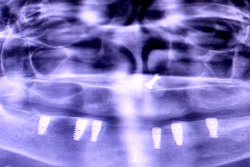

OPG (Pre Treatment)

OPG (Post Treatment)

Case of full mouth rehabilitation All teeth extracted Upper single complete denture and lower Implant supported denture